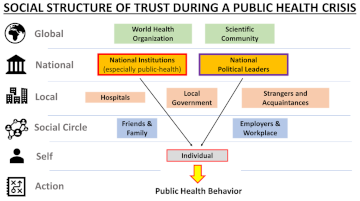

Trust in Institutions, Not in Political Leaders, Determines Compliance in COVID-19 Prevention Measures within Societies across the Globe

2022: Ryan P. Badman, Ace X. Wang, Martin Skrodzki, Heng-Chin Cho, David Aguilar-Lleyda, Naoko Shiono, Seng Bum Michael Yoo, Yen-Sheng Chiang, and Rei Akaishi

In: Behavioral Sciences

A core assumption often heard in public health discourse is that increasing trust in national political leaders is essential for securing public health compliance during crises such as the COVID-19 pandemic (2019–ongoing). However, studies of national government trust are typically too coarse-grained to differentiate between trust in institutions versus more interpersonal trust in political leaders. Here, we present multiscale trust measurements for twelve countries and territories across the West, Oceania and East Asia. These trust results were used to identify which specific domains of government and social trust were most crucial for securing public health compliance (frequency of mask wearing and social distancing) and understanding the reasons for following health measures (belief in effectiveness of public health measures). Through the use of linear regression and structural equation modeling, our cross-cultural survey-based analysis (N = 3369 subjects) revealed that higher trust in national and local public health institutions was a universally consistent predictor of public health compliance, while trust in national political leaders was not predictive of compliance across cultures and geographical regions. Institutional trust was mediated by multiple types of transparency, including providing rationale, securing public feedback, and honestly expressing uncertainty. These results highlight the importance of distinguishing between components of government trust, to better understand which entities the public gives the most attention to during crises.